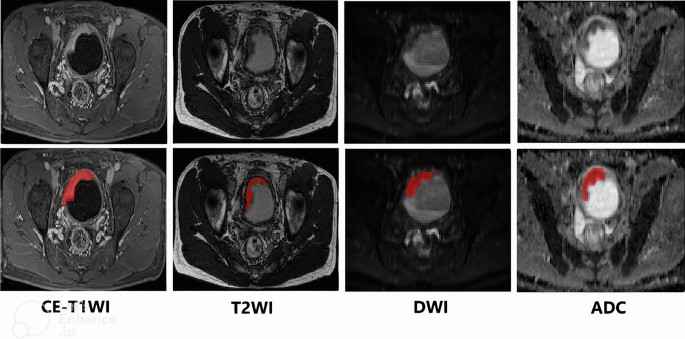

A detailed protocol for MR image acquisition was published earlier [20] and is summarized in Supplementary Methods (Supplementary File 1). A radiologist with over 10 years of experience reading MRIs who was blinded to the histopathologic results and clinical outcomes of the patients manually drew the regions of interest (ROI) on each tumor in various pre-treatment MR images including contrast-enhanced T1-weighted imaging (CE-T1WI), T2-weighted imaging (T2WI), diffusion-weighted imaging (DWI), and apparent diffusion coefficient maps (ADC maps), starting from the first image showing tumor presence and continuing through to the last image. Figure 2 illustrates a representative example of tumor segmentation on imaging, highlighting the delineation of the tumor region for analysis. The entire segmentation process was performed using ITK-SNAP software v.4.2.0 [23].

MIBC patients eligible for platinum-based NAC were prospectively included. Tumor regions were manually segmented from pre-treatment MRI sequences (CE-T1WI, T2WI, DWI, ADC maps). Radiomics features and clinical variables were extracted. Least Absolute Shrinkage and Selection Operator (LASSO) was used for feature selection, and multiple ML classifiers were trained using stratified fivefold cross-validation. The area under the receiver operating characteristic curve (AUC-ROC), sensitivity, specificity, precision, and F1 scores were calculated.